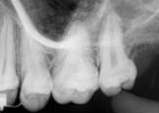

antes depois